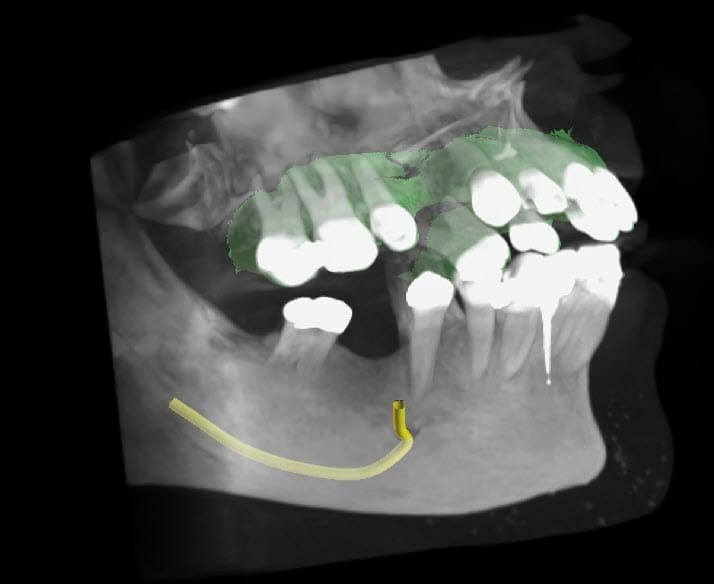

Cone Beam X-ray, or CT Scan

When we need a lot more detail, or different perspectives and angles, we take a CT scan, also called a cone beam or 3D x-ray. Cone beam images are quite different from the other types, because they’re taken in slices. Computer algorithms turn those slices into a 3D images. That 3D x-ray can be rotated in every direction, and we can scan through it up/down, forward/back, and side-to-side. They’re really quite incredible!

These cone beam views are of the same patient above, with the panoramic x-ray. Now we see the true size and shape of those unusual areas.

3D X-Rays for Dental Implants

When planning dental implants , we have to know if the bone is both wide and tall enough. If it is, great! If not, then you may need a bone graft or sinus lift to build up the bone. Without the 3D views, we can’t know that. We can also see other important anatomy, like the big nerve in your lower jaw (the yellow line). We really don’t want to run into that!